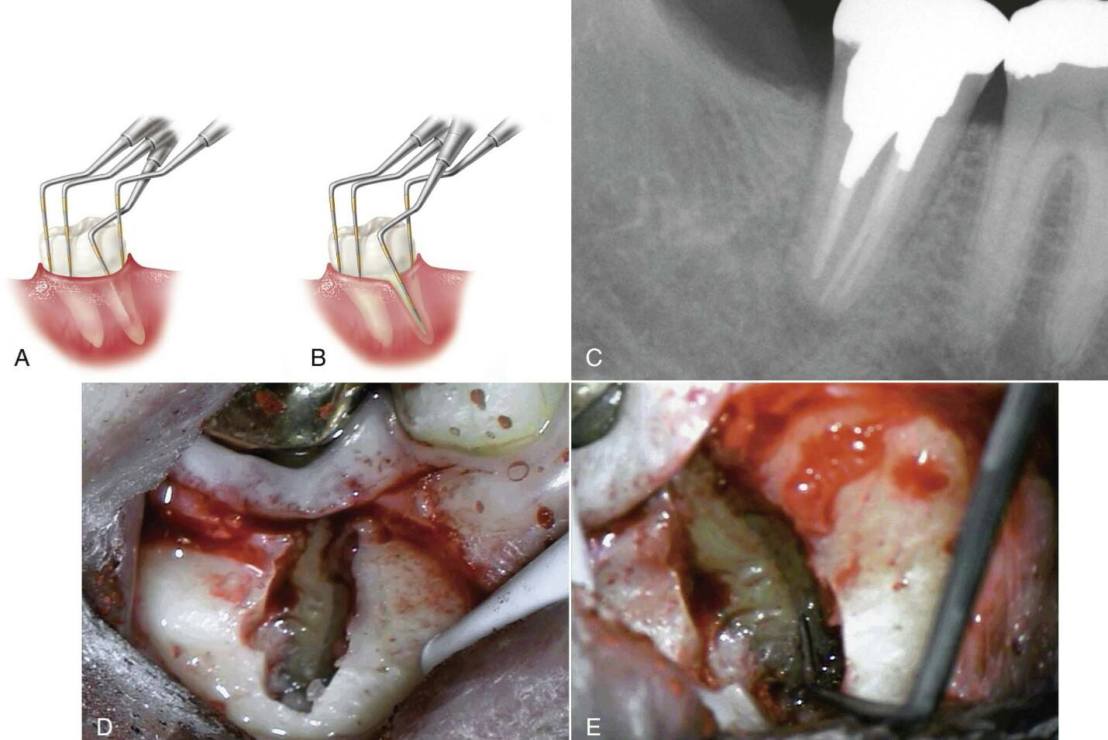

ลักษณะการ Probing ที่เป็นลักษณะเฉพาะ deep,narrow และเฉพาะจุด เพราะเกิด bone dehiscence ในตำแหน่งที่มี Vertical root fracture

การฉายแสงหรือใช้ Dye penetration ช่วย (โดยส่วนตัววิธีนี้ทำให้เกิด False positive เยอะมาก ควรใช้อย่างระมัดระวังครับ)

อธิบายคือ แสงเสมือนเป็นคลื่นที่เดินทางผ่านตัวกลางที่สม่ำเสมอ แต่เกิดการเปลี่ยนแปลงของดัชนีหักเหโดย crack ทำให้การดูดซึมและสะท้อนในตัวกลางที่เปลี่ยนไป เห็นเป็นชิ้นส่วนที่สว่าง+crack+ชิ้นส่วนที่มืดลง